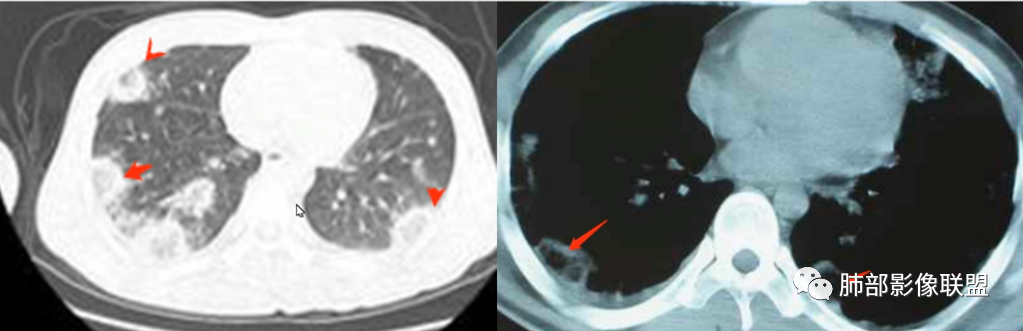

2.影像上肺多发混合密度片影,随机分布,胸膜下分布优势,病灶边界大多隐约可辨,偏柔和,动脉血管影穿行,未见钙化、液化空洞、或明确气囊影,未见树芽征。

3.影像方面:双肺多发病灶,随机分布,且有相当部分沿胸膜下,是可以符合血流感染的。

2.表现多样,多种影像表现可同时出现,如斑片状影、小点状影、结节影、肺气囊等可在CT片上同时见到;

3.病灶比较广泛,多个肺野出现同时受累;

4.容易在短期内出现散在的肺气囊或多发的脓肿病灶;

1.外围分布,胸膜下为主,两肺弥漫结节或胸膜下楔形影,边界清,周围伴有GGO

2.反晕征:往往紧贴胸膜,并且胸膜侧无环,周围GGO